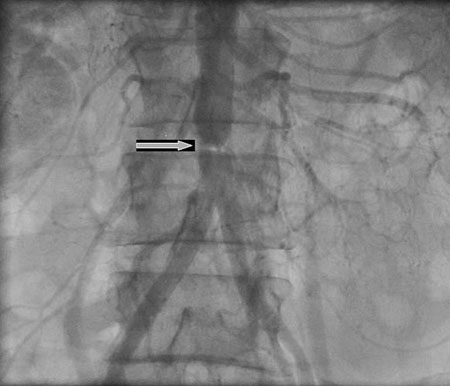

A coarctação abdominal ocorre na aorta abdominal e pode estar associada ao estreitamento dos vasos aórticos abdominais.[Figure caption and citation for the preceding image starts]: Coarctação abdominalN. Pal, D. McEneaney. BMJ Case Reports 2009 [Citation ends].